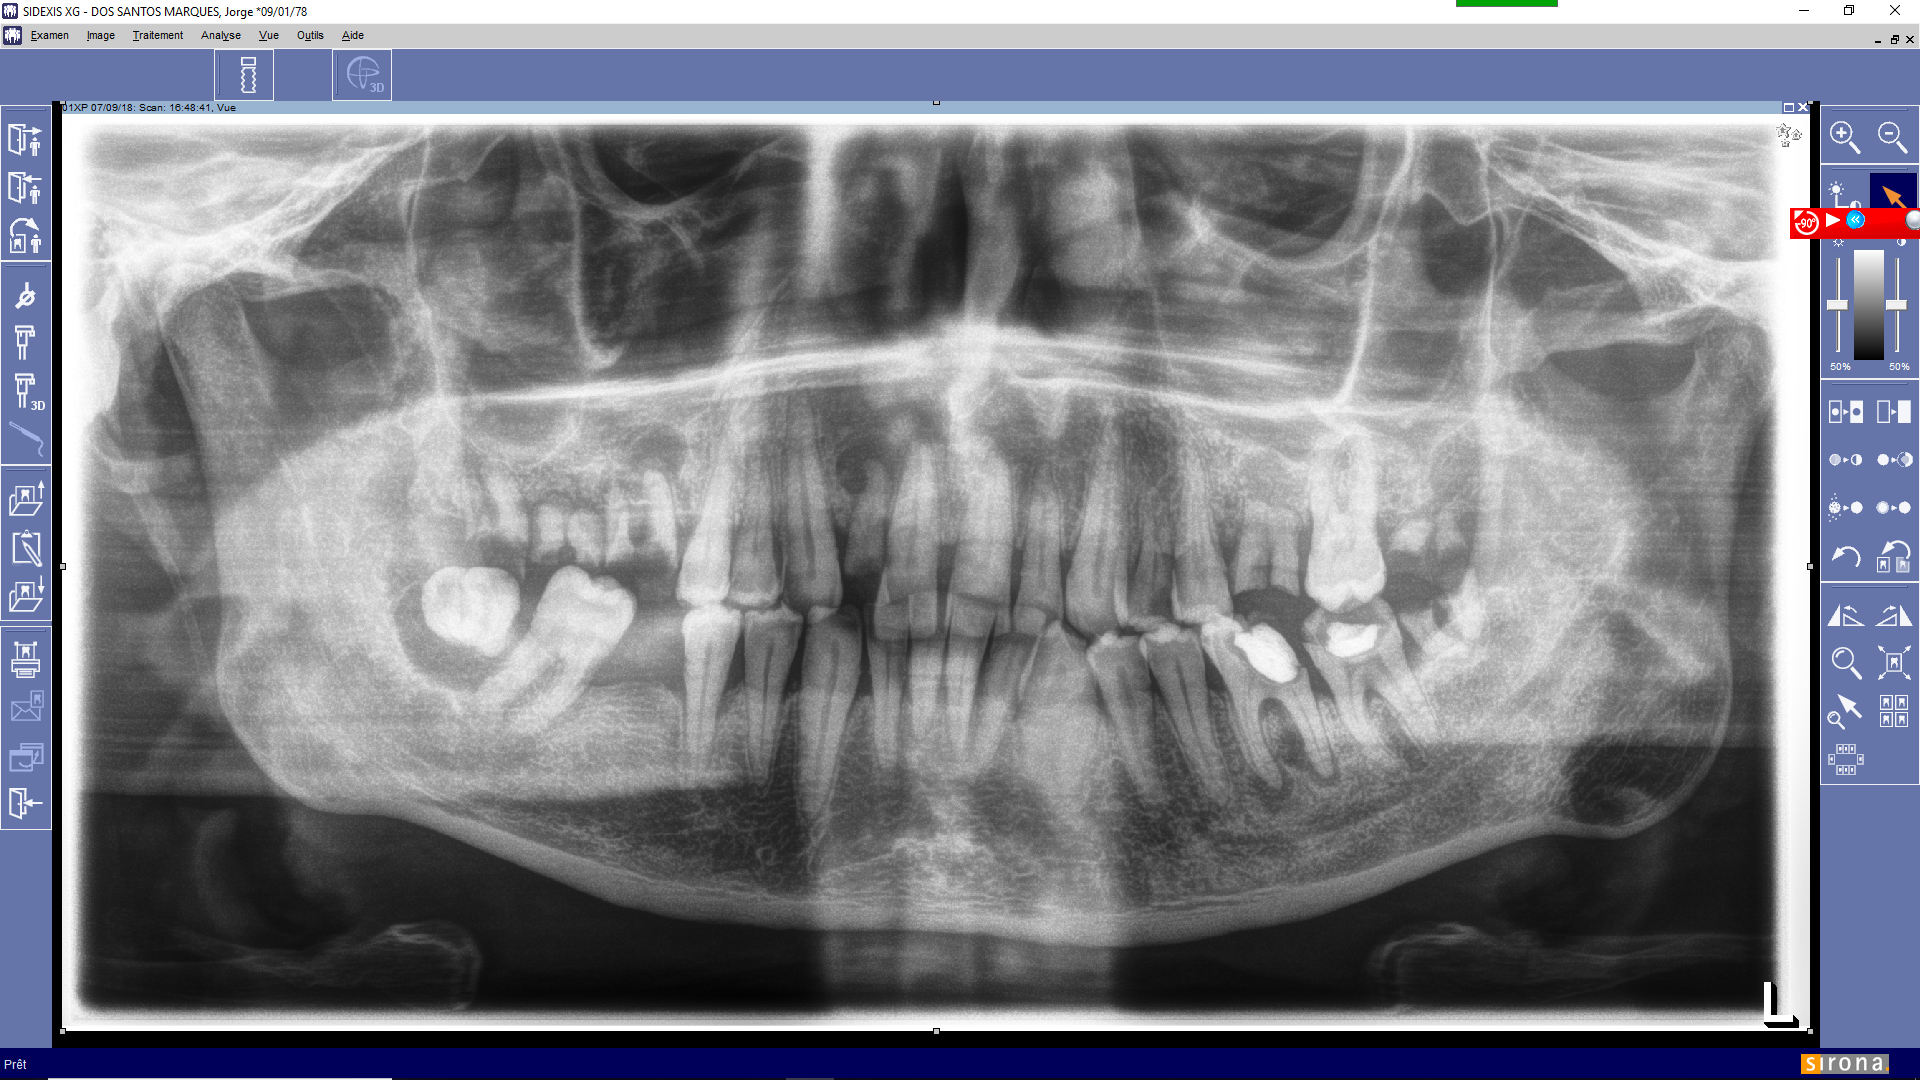

Pour abreuver le fil, un exemple tout chaud (5 minutes), cellulite haut droite. Cela au rait pu être ailleurs.

Donc pano avant de voir le patient...

Aujourd'hui, j'en ai trois comme cela...

Exemple de pano préintervention ctycek - Eugenol